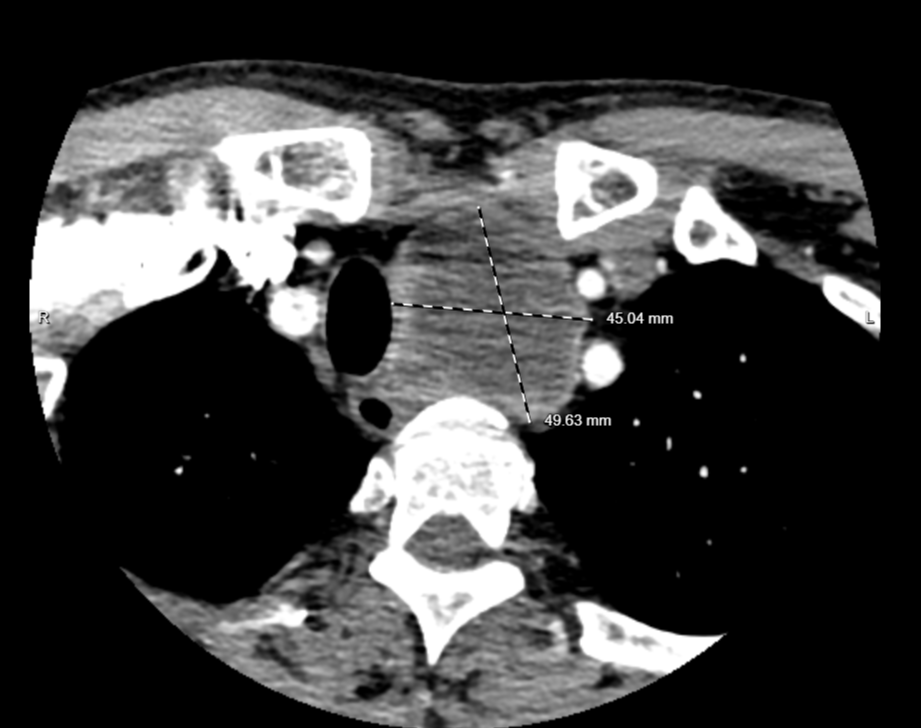

检查见肿物较大,位于主动脉弓后方水平,已压迫气管、食管使其移位,最大直径约5.0cm,未排除神经鞘瘤可能。